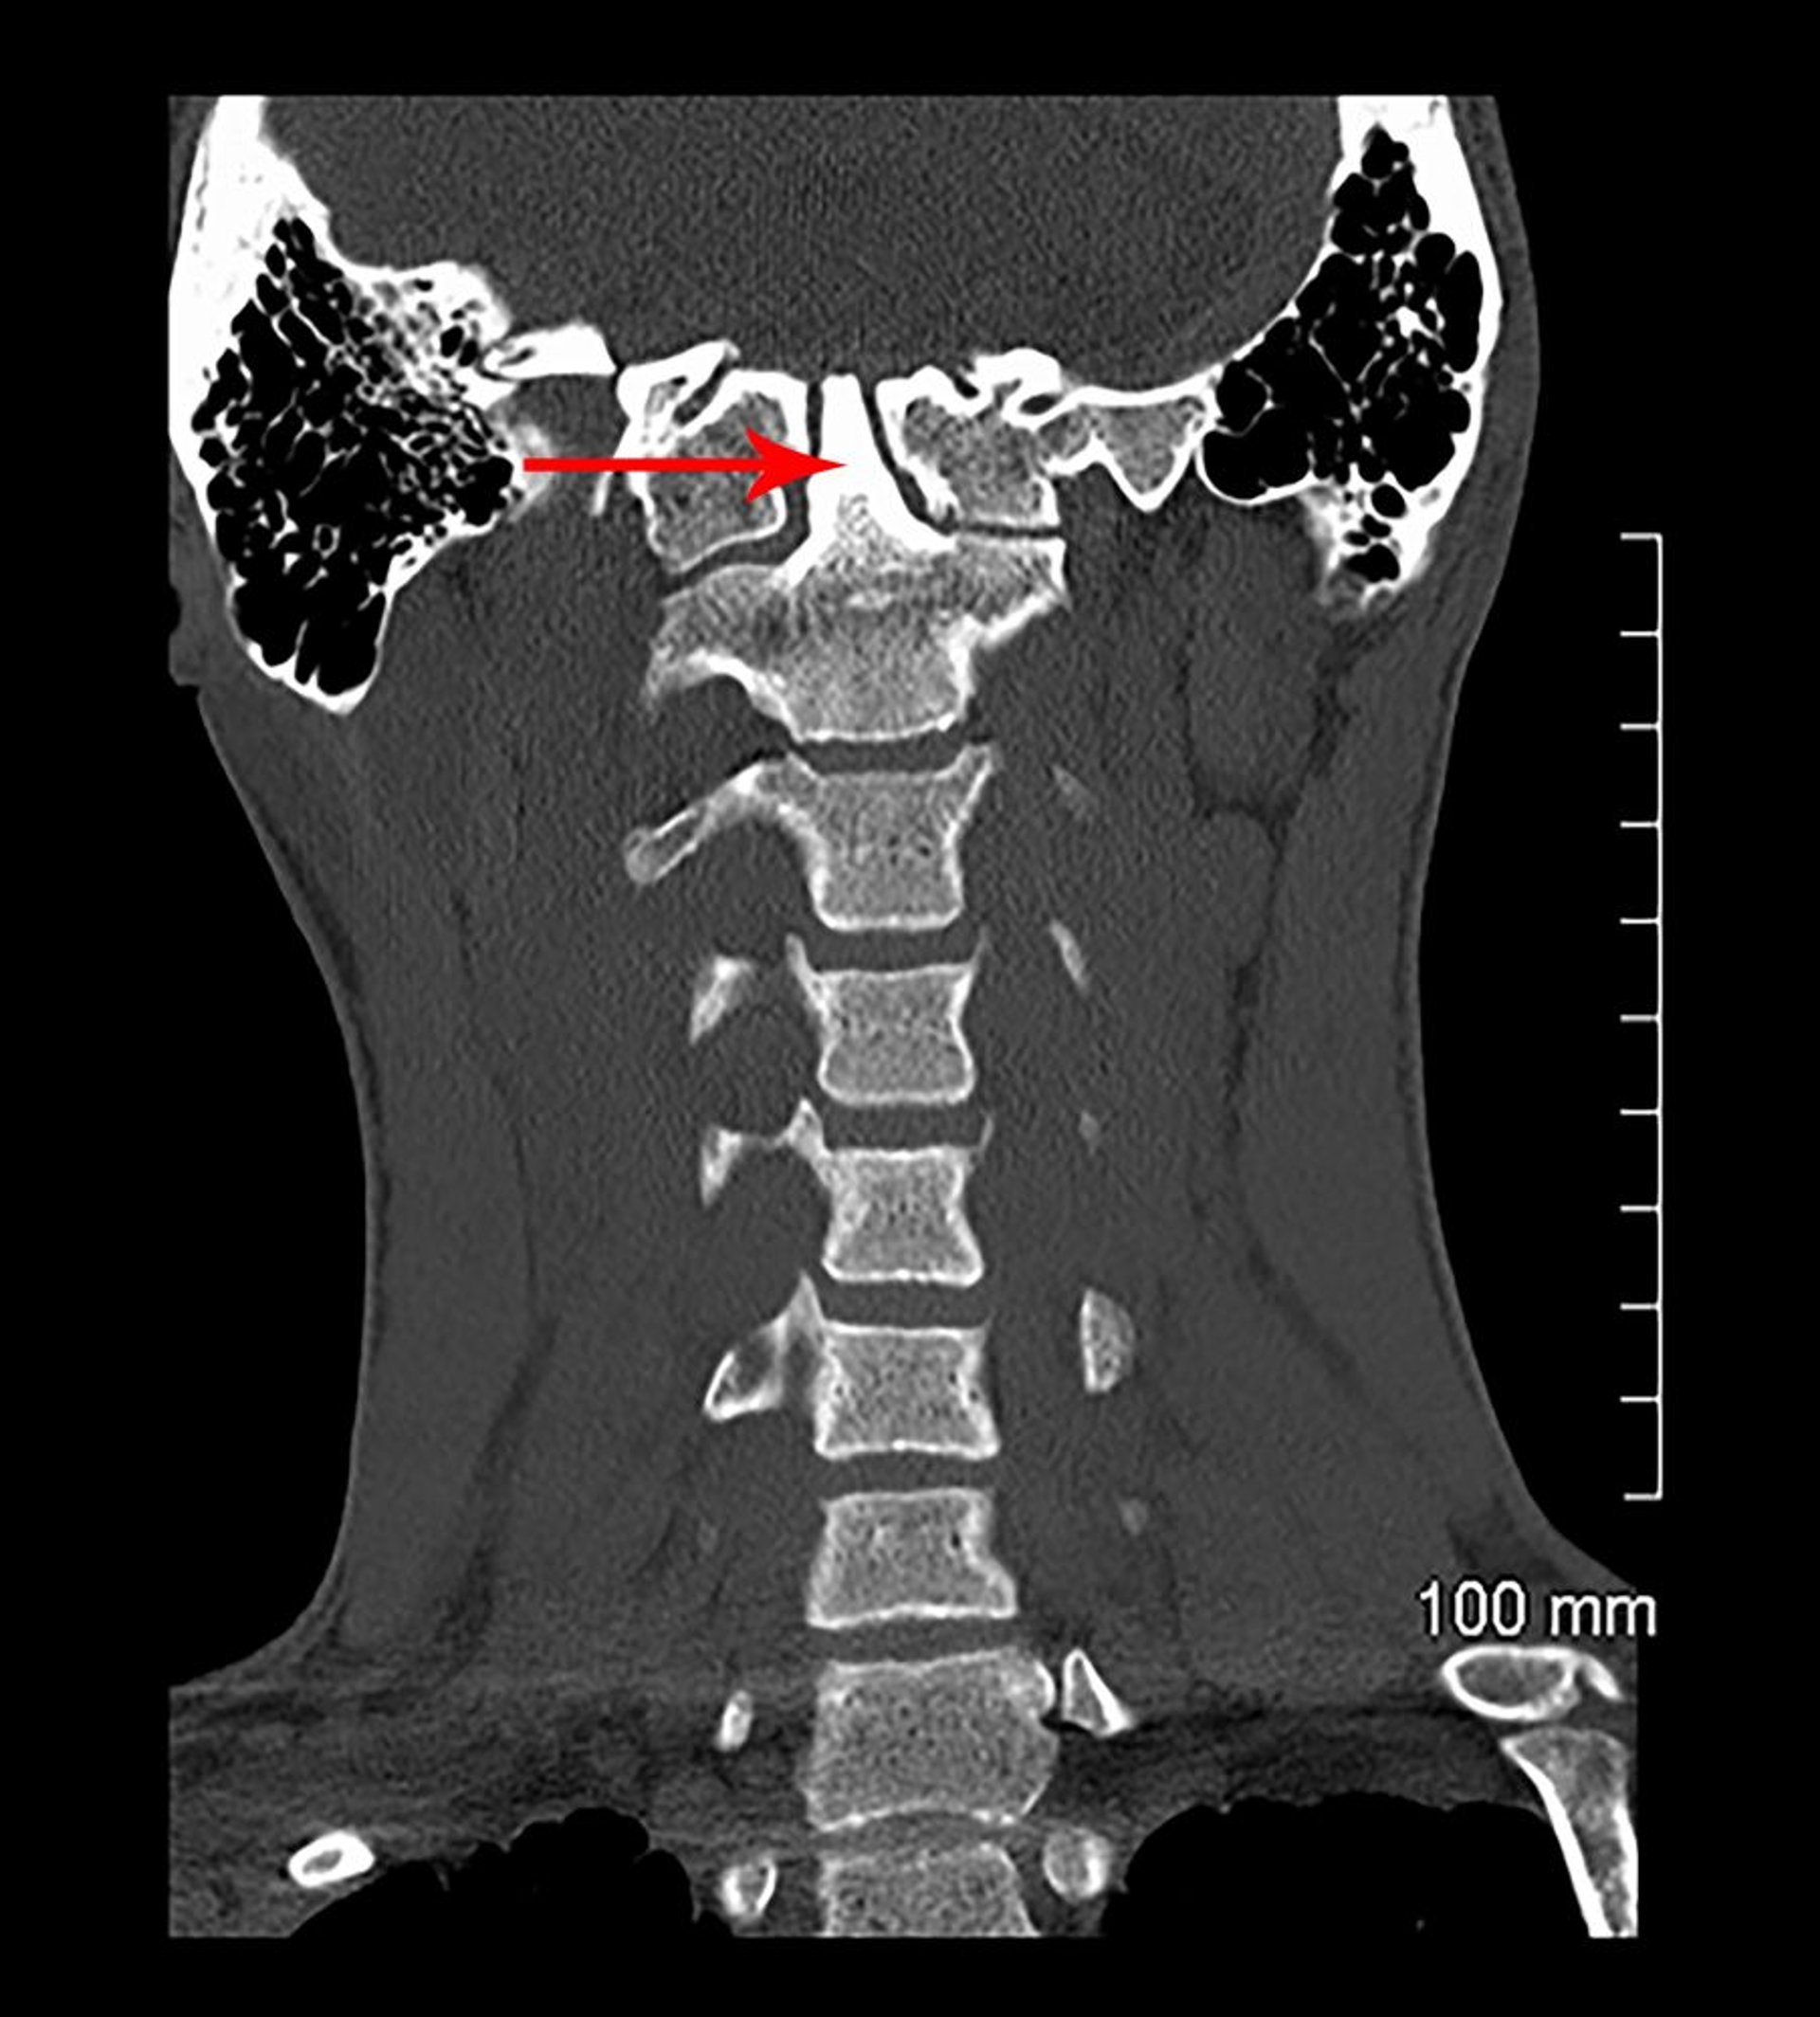

Invaginazione basilare e assimilazione congenita (TC)

In questa vista coronale di una scansione TC, C1 è fuso alla base del cranio (congenitamente). Il processo odontoideo (indicato dalla freccia) si estende nella base del cranio (invaginazione basilare).